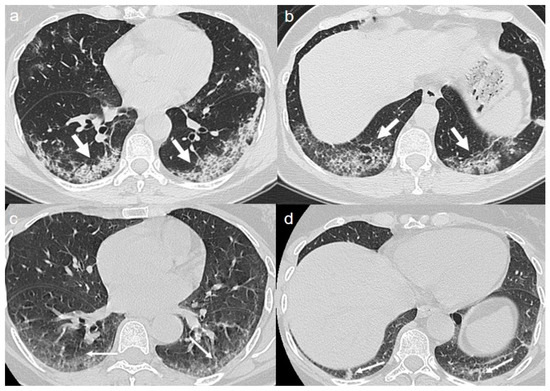

On admission, chest CT showed a “crazy paving pattern” peripherally located in the upper left lobe and in the lower lobes (Figure 6a,b).

A CT at 4 months from the onset of symptoms showed bilateral persistence of mixed pattern characterized by interlobular septal thickening and patchy GGOs (Figure 6c,d).

Figure 6. (a,b) CT shows a “crazy paving pattern” peripherally located in the upper left lobe (arrow in a) and in the lower lobes (arrows in b). (c,d) CT after 4 months from the onset of symptoms shows persistence of mixed pattern characterized by interlobular septal thickening (thin arrows in c) and patchy GGOs (thin arrows in d).